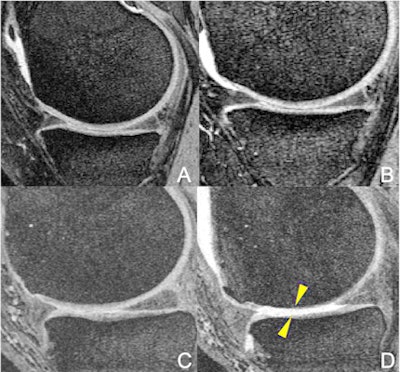

MR images of the right knee (A, B, C, D) at baseline (A, C) and after 48 months (B, D). An overweight 47-year-old woman in the elliptical trainer group (A-B) and an overweight 64-year-old man in the racket sports group (C-D). The man in the racket sports group developed severe cartilage damage at the femur and tibia bones (arrowheads). In contrast, no cartilage damage was seen in the woman in the elliptical trainer group (A-B). Images and caption courtesy of the Radiological Society of North America.The patients kept records of participation in six types of physical activity: ball sports, bicycling, jogging/running, elliptical trainer, racket sports, and swimming. Each person underwent a baseline MRI scan and a follow-up exam four years later. The investigators assessed any changes in the patients' knees using the Whole-Organ Magnetic Resonance Imaging Score.

Racket sports increased knee joint denigration much more than, for example, using an elliptical trainer; overall score also increased significantly more in the racket sports group compared with the jogging/running group. Those study participants who also played racket sports had significantly greater degeneration in the medial tibial cartilage compartment, where arthritis typically begins to appear.